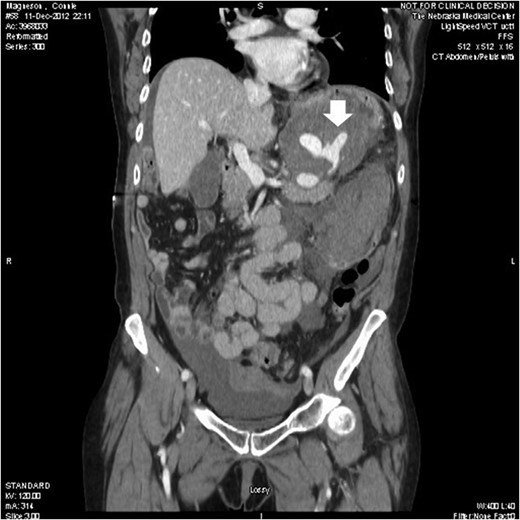

A 65 -year-old woman with a known history of multiple splenic and hepatic aneurysms was admitted to our hospital in October 2012 with acute abdomen. Abdominal computed tomography angiography showed rupture of splenic aneurysm with active extravasation of contrast and associated large left upper quadrant hematoma with small hemoperitoneum (Fig. 1). Visceral angiogram confirmed the presence of three fusiform aneurysms involving midsplenic artery (Fig. 2). The distal most aneurysm demonstrated large extravasation (Fig. 3). Coil embolization of the proximal and midsplenic artery aneurysm was performed using multiple Nester coils (Cook Medical, USA) with cessation of antegrade flow (Fig. 4). Attempt to access distal portion of the splenic artery was unsuccessful. She recovered well and was discharged 4 days later. In December 2016, she was admitted with dyspepsia and severe iron deficiency anemia requiring blood transfusion. A colonoscopy and upper endoscopy were performed which showed the presence of metallic coils in the stomach (Fig. 5). The patient subsequently underwent a combined upper endoscopy and laparoscopy. Three 5 mm ports were used to expose the lesser sac in event of hemorrhage during extraction of the coil endoscopically. An atraumatic bowel clamp was placed distal to the Treitz ligament to prevent insufflation of the small bowel. Upper endoscopy was performed using CO2 insufflation and the Nester coils were retrieved using rat tooth forceps (Fig. 6). There was no bleeding in the lesser sac after removal of the coils. A leak test was performed to rule out gastric perforation. She had an uneventful recovery and was discharged the next day.

Computed tomography showed three saccular splenic artery aneurysms with a large left upper quadrant hematoma (block white arrow) and blush from distal splenic aneurysm.